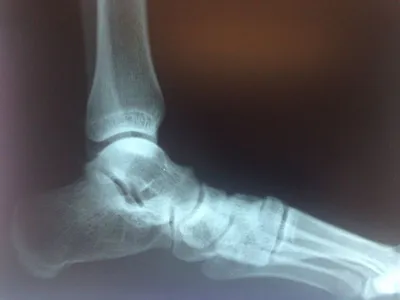

The images below demonstrate Lis Franc's ligament rupture with increased spacing between the medial cuneiform and the intermediate cuneiform. The ligament is attached between the base of the 2nd metatarsal and the lateral aspect of the medial cuneiform (left). The post-surgical repair with screw fixation (right) shows reduction in that aforementioned space between the cuneiforms re-establishing the stability of the medial midfoot.